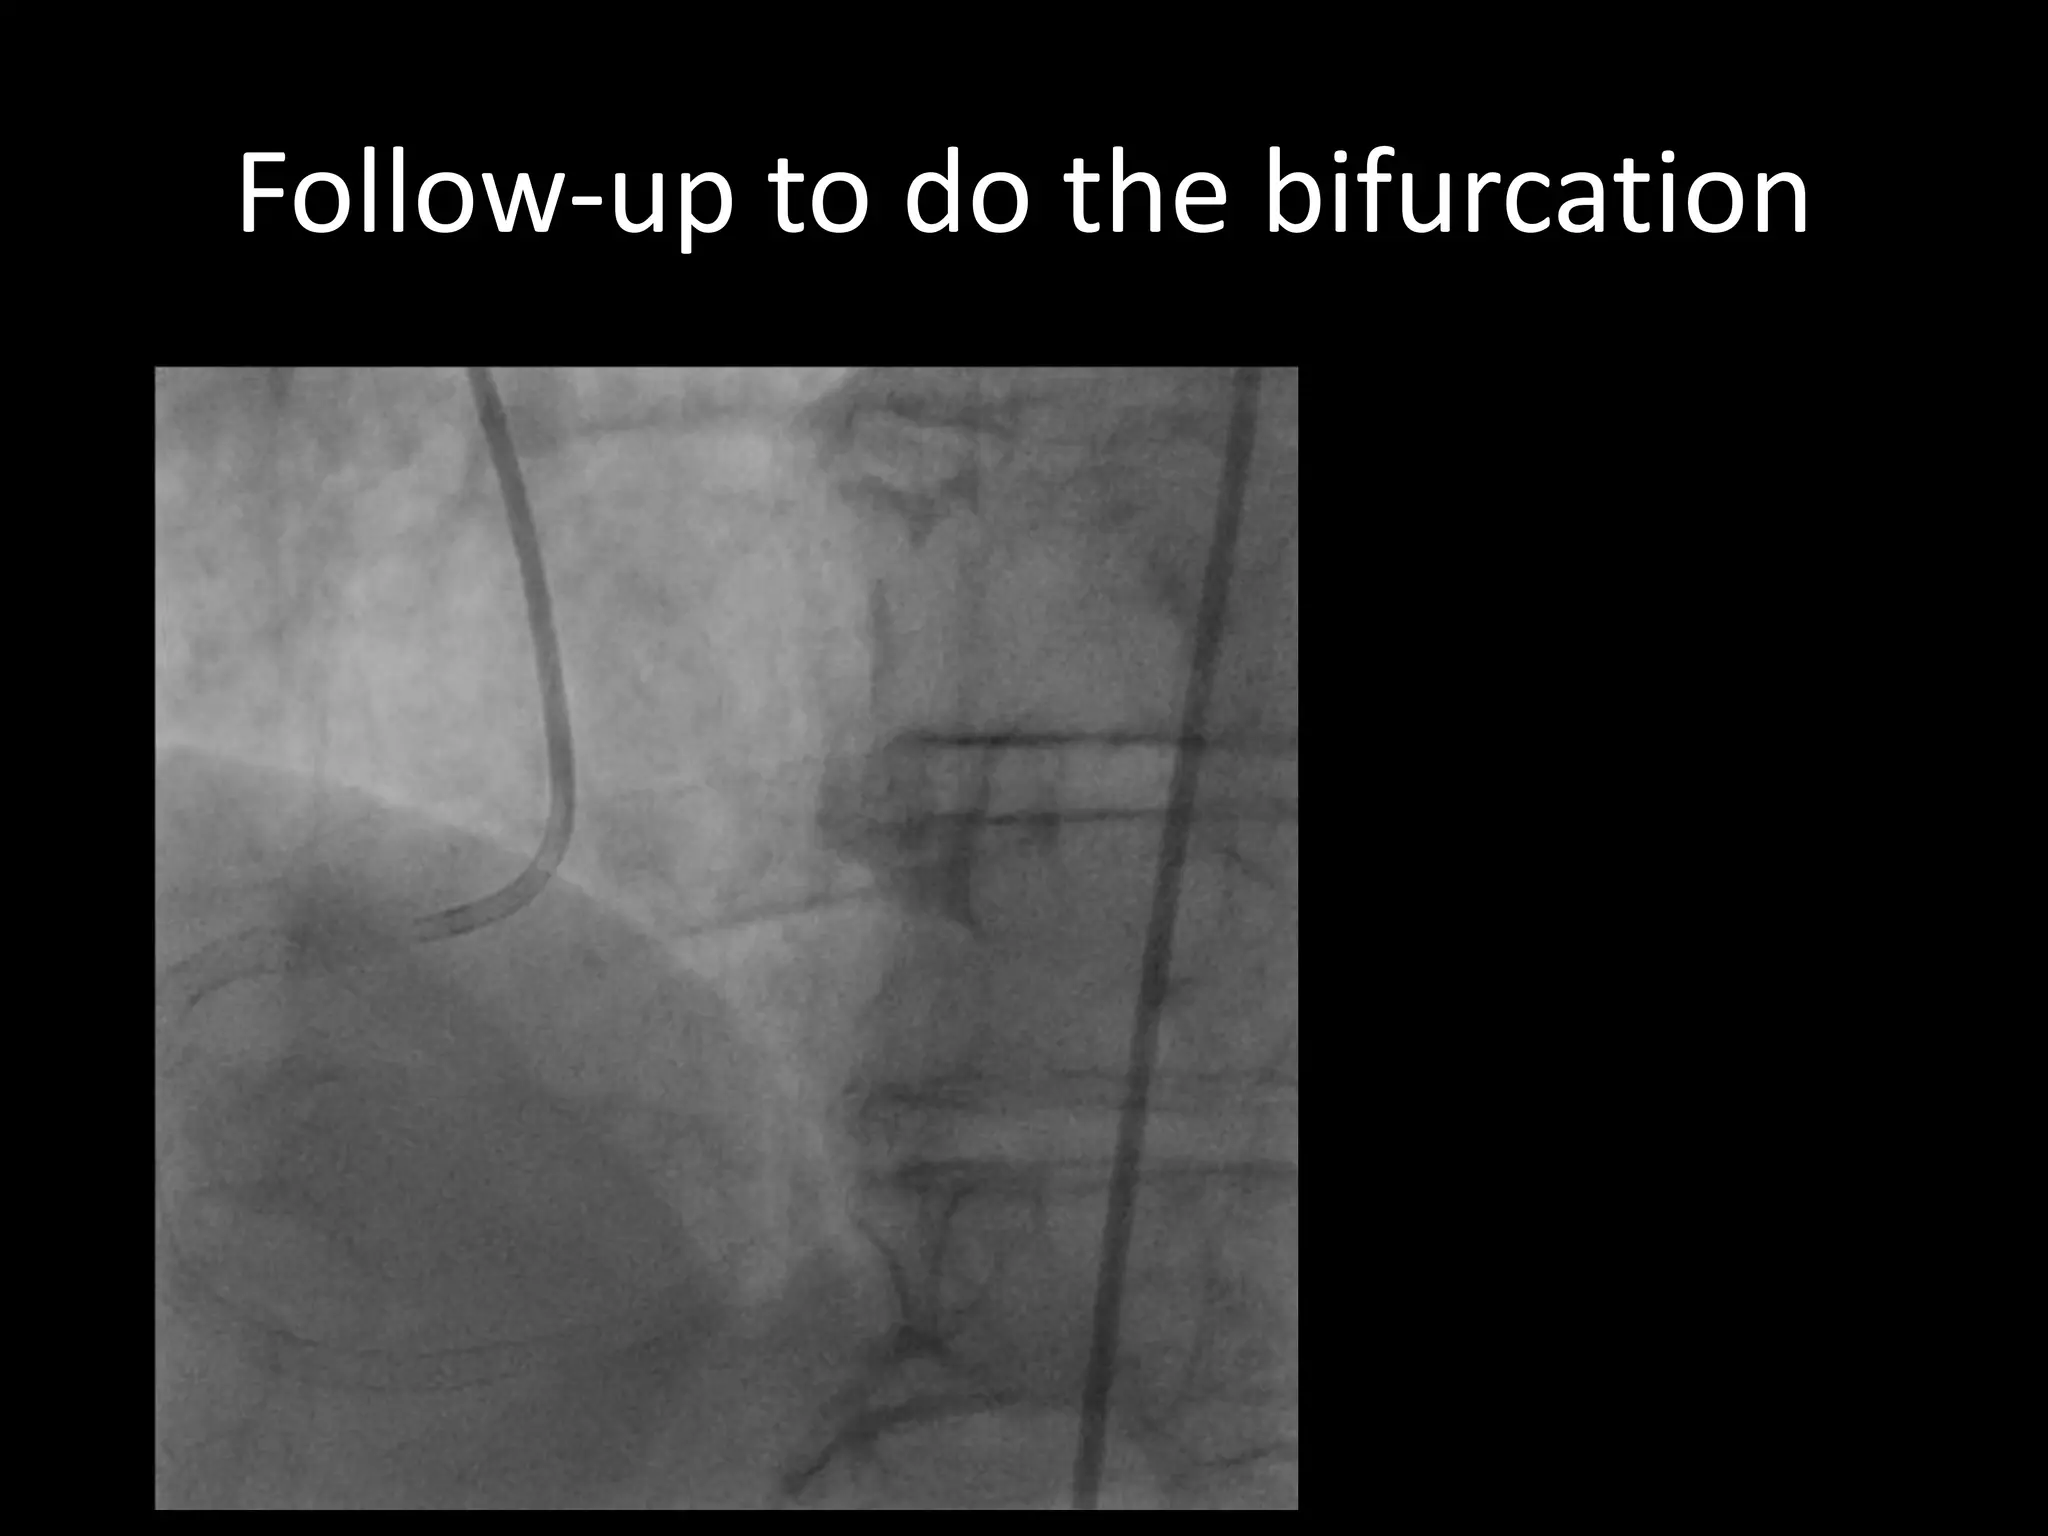

This document provides guidance on evaluating the feasibility of percutaneous coronary intervention (PCI) for a chronic total occlusion (CTO). Key factors to consider include: the patient's tolerance for a long procedure, contrast load, and radiation exposure; the CTO's proximal cap ambiguity, length, distal landing zone, and presence of interventional collaterals; and ensuring good quality angiography. With adequate planning and use of appropriate CTO techniques, feasibility is nearly always present for symptomatic patients. Success rates of CTO-PCI are reported to be 94% when using a planned approach.